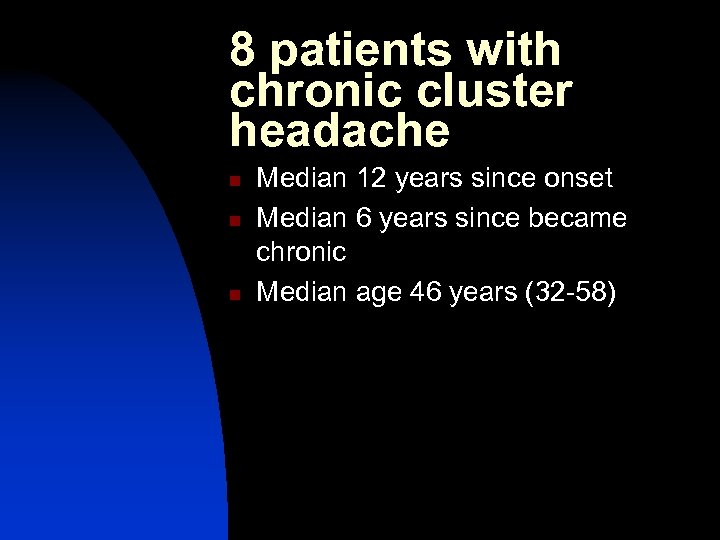

Results of ONS in cluster headache n Burns B; Watkins L; Goadsby P. Lancet 2007 369: 1099 -1106 Treatment of medically intractable cluster headache by occipital nerve stimulation: long term follow up of eight patients

8 patients with chronic cluster headache n n n Median 12 years since onset Median 6 years since became chronic Median age 46 years (32 -58)